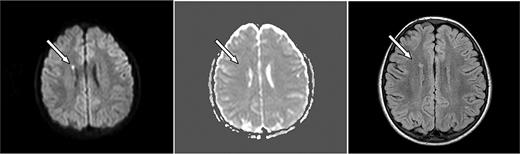

Axial MRI images of case 4. A 6-year-old boy with SCD and acute chest syndrome with hgb = 4.1 g/dL showing (left, arrow) an area of restricted diffusion on DWI images with an ADC correlate (middle). Follow-up FLAIR MRI 4 months later (right) shows a lesion corresponding to the affected area on the DWI.

ASCIE were identified by DWI in 4 (18.2%) of 22 children with SCD and 2 (6.7%) of 30 without SCD (P = .382, Table 1). All had areas of restricted diffusion on DWI with corresponding areas of decreased signal on ADC map. There were corresponding abnormalities on the initial FLAIR images in 4 of 6. DWI lesions were subcortical or in the deep white matter (Figures 1–2). One patient had deep white matter DWI lesions and a lesion in the splenium of the corpus callosum without history of seizure. Two of the 6 patients had multiple DWI lesions, 4 had solitary lesions.

Follow-up MRI studies (Figures 1–2) were obtained 2.5 to 7 months later for other clinical indications for 4 of 6 of the patients with ASCIE; 3 had lesions on FLAIR images consistent with SCI in locations corresponding to the ASCIE on the initial study MRI (Table 1) and thus meet the definition of acute SCI. All 3 had SCD. Notably, the patient without a corresponding lesion on follow-up imaging also had no FLAIR correlate on the initial study MRI. This patient did not have SCD. We believe this to be a transient, reversible ASCIE.7 Magnetic resonance angiography (MRA) was not part of our study protocol but was obtained for the clinically indicated follow-up studies for 4 of 6 of the patients with ACSIE and was normal in 3, with 1 patient demonstrating subtle vascular irregularities in the internal carotid artery and middle cerebral artery ipsilateral to the ASCIE (Table 1).